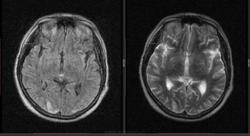

Мужчина 1964 г.р. Жалобы на нарушение памяти, снижение зрения и кратковременную потерю сознания, температура нормальная.

Я думаю что это может быть какой нибудь васкулит, либо Posterior Reversible Encephalopathy Syndrome, о чем можно думать в данном случае?

eto pres

Я представлял синдром с более выраженным изменением сигнала от белого вещества и меньшим - коры.